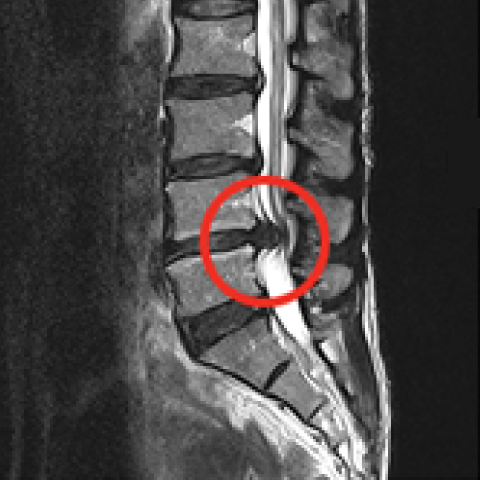

터진 디스크를 내시경으로 제거하는 모습